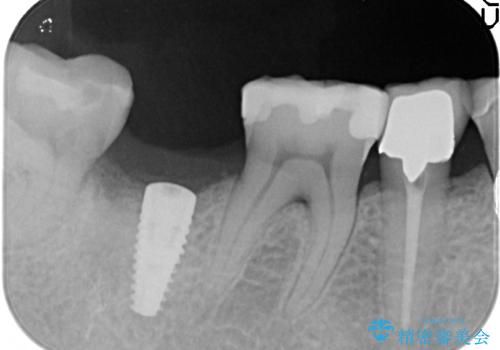

- 右下の奥歯をかぶせ物がとれたまま放置しているところに歯を入れたいとのことで来院されました。

精査すると保存が難しいため抜歯をして、インプラントを埋入、かぶせ物を装着する計画としました。